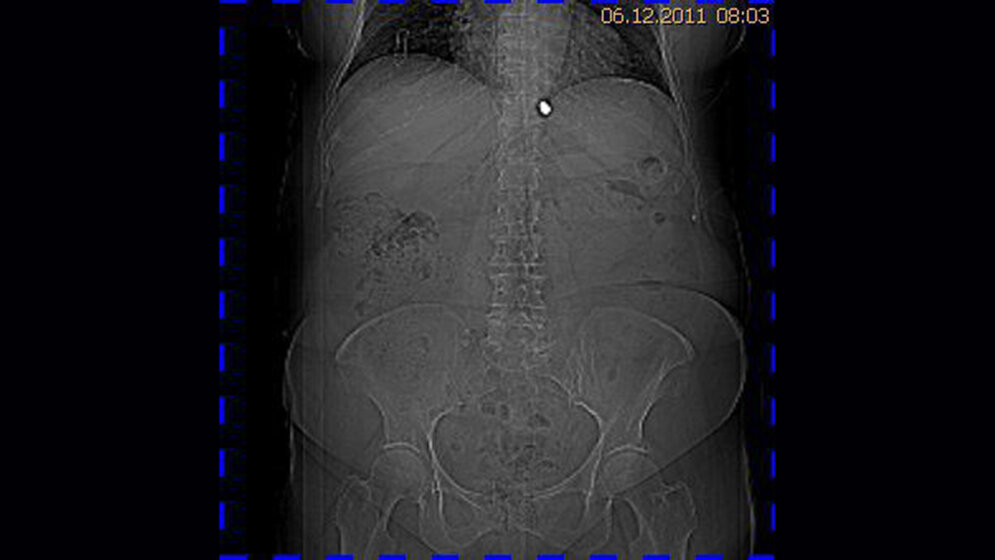

Zufallsbefunde: Schussverletzung (Lungensteckschuss)

Schnittbilddiagnostik der Wirbelsäule (3.9)

Metallartefakte werden in der Computer- oder Kernspintomographie häufig gefunden. Dabei kann es sich um operativ bedingte Clips an kleinen Gefäßstrukturen handeln, um Teile von Gefäßprothesen oder auch um Gelenkprothesen.

Die Radiologen können bei Patienten mit Schussverletzungen Diagnostik und Behandlung sichern. Die Röntgenaufnahmen, CT, Angiographie und MRT lokalisieren das Projektil und den Schusskanal,

stellen Begleitverletzungen fest, Knochen- und Projektilfragmente.